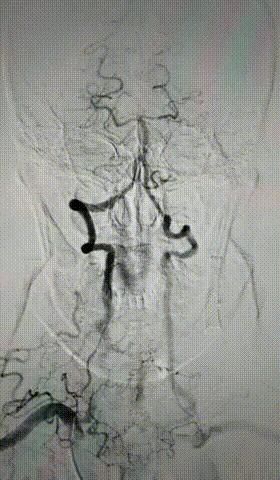

除了内科治疗外,若缺血症状严重可以考虑手术治疗,如血管内支架、血管内膜剥离或血管重建术等,其中对于症状性锁骨下动脉狭窄≥50%患者,血管内支架治疗是首选的治疗方法。

请点击输入图片描述